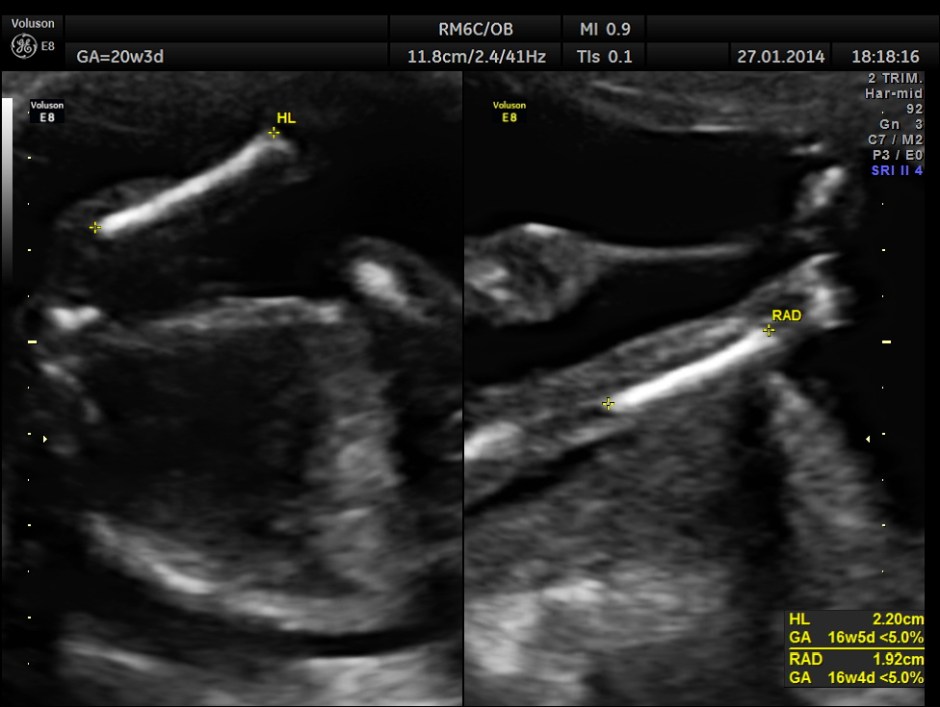

As it can be seen , the GA was around 20 weeks , but the AUA was around 17 weeks. All parameters – BPD, HC, AC, FL are < 2.3 %tile and all other long bones are < 5.0 %tile.